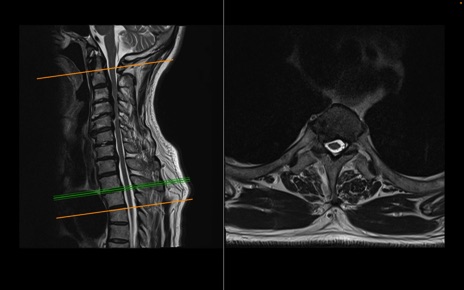

頚椎MRI

T2WI(横断像)

T2WI(矢状断像)